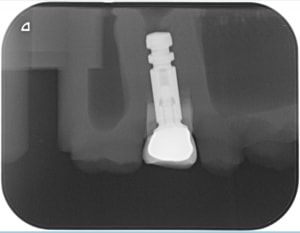

Capture_d_écran_9_zduz7c.png